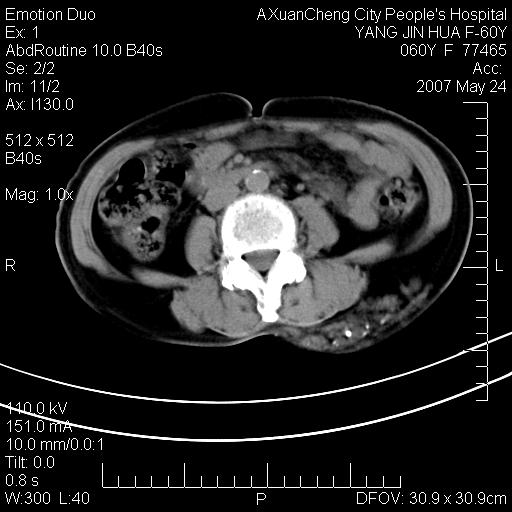

发现左侧腰背部包块40余年,逐渐长大,质软,局部表面可见扩张的血管影

左背部皮下良性肿瘤,密度不均,边界不清,内有脂肪、钙化,增强扫描无明显强化,血管平滑肌脂肪瘤?进一步诊断有困难,建议穿刺活检。

左侧背部皮下混杂密度肿块,结构较疏松,边缘欠光整,内有多发斑点状钙化,考虑:皮下血管瘤。